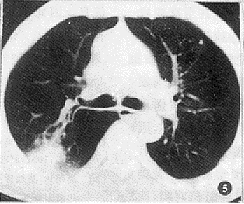

2.6 病变周围情况:球形肺炎中有13例病变与肺门之间有多条增粗的血管影相连(62%)(图4),3例病变附近有异常增多增粗的血管影。7例病变所属段及亚段支气管壁增厚(图5)。6例早期病变周围有小片状浸润影(非胸膜侧),2例晚期病变周围有索条影。周围型肺癌中9例病变邻近亦可见小片状浸润影,但局限于胸膜侧。7例血管连接征阳性,但不局限于胸膜侧,且多为单一血管。3例周围肺野有散在分布的多发小结节影(转移灶)。1例病变所属支气管呈不规则狭窄。

图5 右上叶后段球形肺炎,亚段及次亚段支气管壁均匀增厚